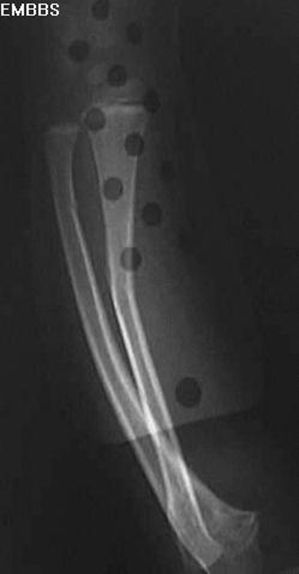

肱骨干骨折

直接暴力–横断骨折或粉碎骨折,间接暴力–斜形、螺旋形或蝶形骨折,肱骨上段的骨折–近折端向前内侧错位–远折端向上、外错位,肱骨中段骨折–近折端向外、前方移位–远折端向上移位–骨折端重叠错位。